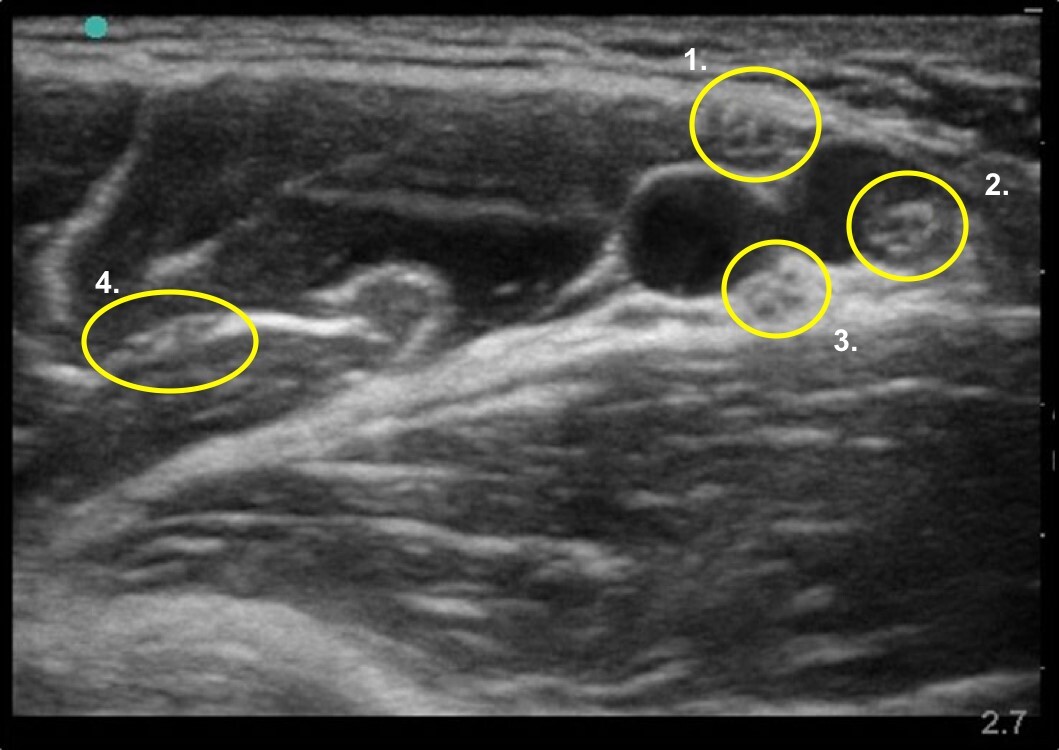

Axillary Nerves Image

Median Nerve

Radial Nerve

Ulna Nerve

Musculocutaneous Nerve